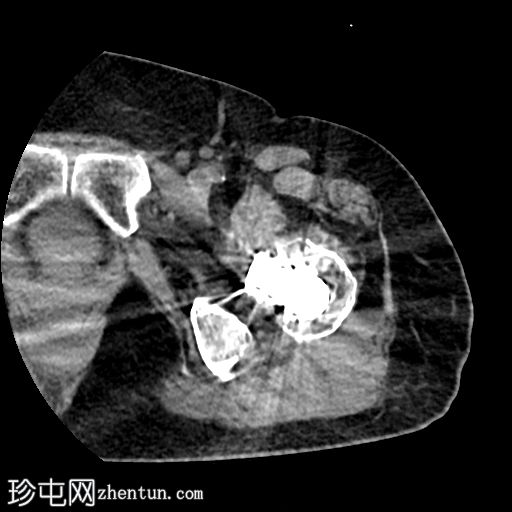

CT

轴位片

平扫

左侧全髋关节置换术。大转子基底部可见轻微移位的假体周围骨折。

大转子滑囊积液,可见脂肪-液体平面。